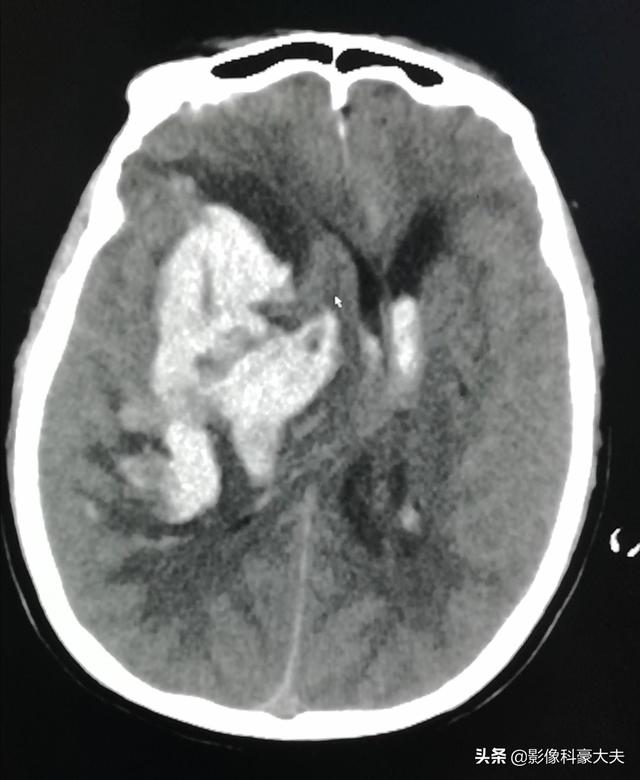

これは、午前3時にパートナーによって意識不明の状態で発見された66歳の男性患者が、大量の右側脳出血を起こしたためであった。しかし、CTのない時代には、この疾患の死亡率は非常に高かった。CTを用いたタイムリーで正確な定量的・局所的診断により、適時の穿刺とドレナージが可能となり、性温存と合併症の軽減が期待できる。